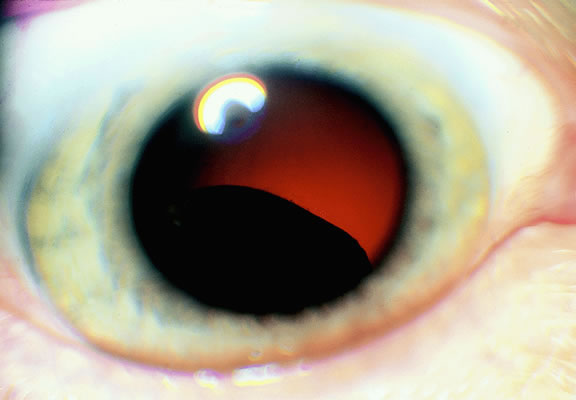

Melanocytic tumors of the uvea are classified into four groups on the basis of cytology. Tumors composed entirely of spindle A cells or even blander nevus cells are classified as spindle cell nevi. Tumors composed of a mixture of malignant spindle A and spindle B cells are called spindle melanomas. Melanomas of mixed cell type contain a mixture of spindle and epithelioid melanoma cells (Fig. 42). Some laboratories specify the predominant cell type found in a mixed cell melanoma, for example, reporting mixed cell, predominantly spindle if only a few epithelioid cells are present. Epithelioid melanomas are composed predominantly of epithelioid cells. They are relatively rare and have the poorest prognosis. Most medium- and large-sized melanomas contain a mixture of spindle and epithelioid cells. In the COMS histopathology study, 86% of the posterior melanomas were classified as mixed cell type, 8% were of spindle cell type, and 5% were epithelioid.84 The association between cytology and mortality is known as the Callender classification.90 (See later section on prognostic factors.)

Fig. 42. Uveal melanoma, mixed cell type. Mixed cell melanomas are composed of a mixture and spindle and epithelioid cells. (Hematoxylin-eosin, × 250.)